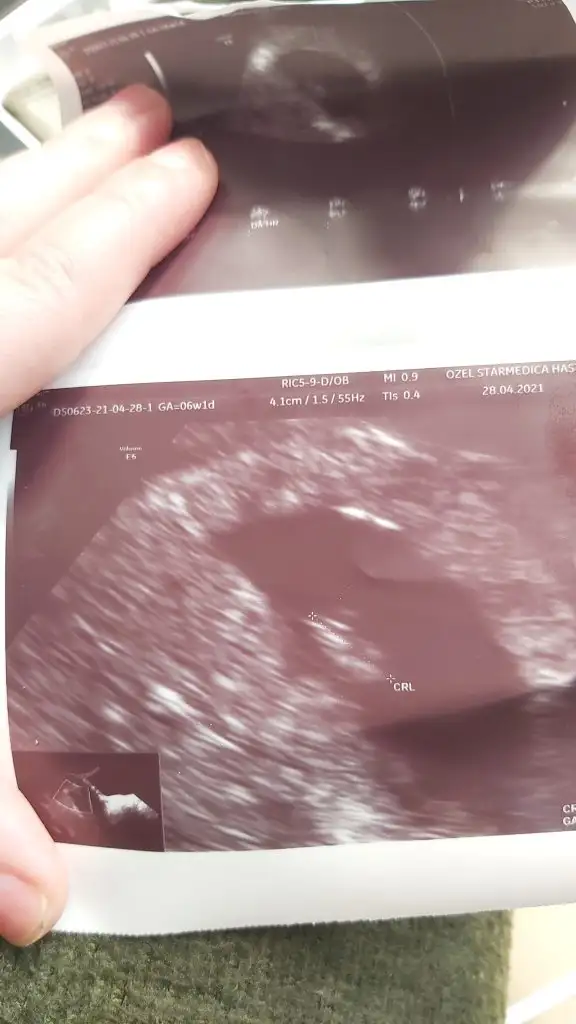

Gebelik kesesi var bebek yok

Minigimi gördük bugün cok şükür kızlar kalp atisinida duydum

• IMG-20210428-WA0001.webp

23,7 KB · Görüntüleme: 381